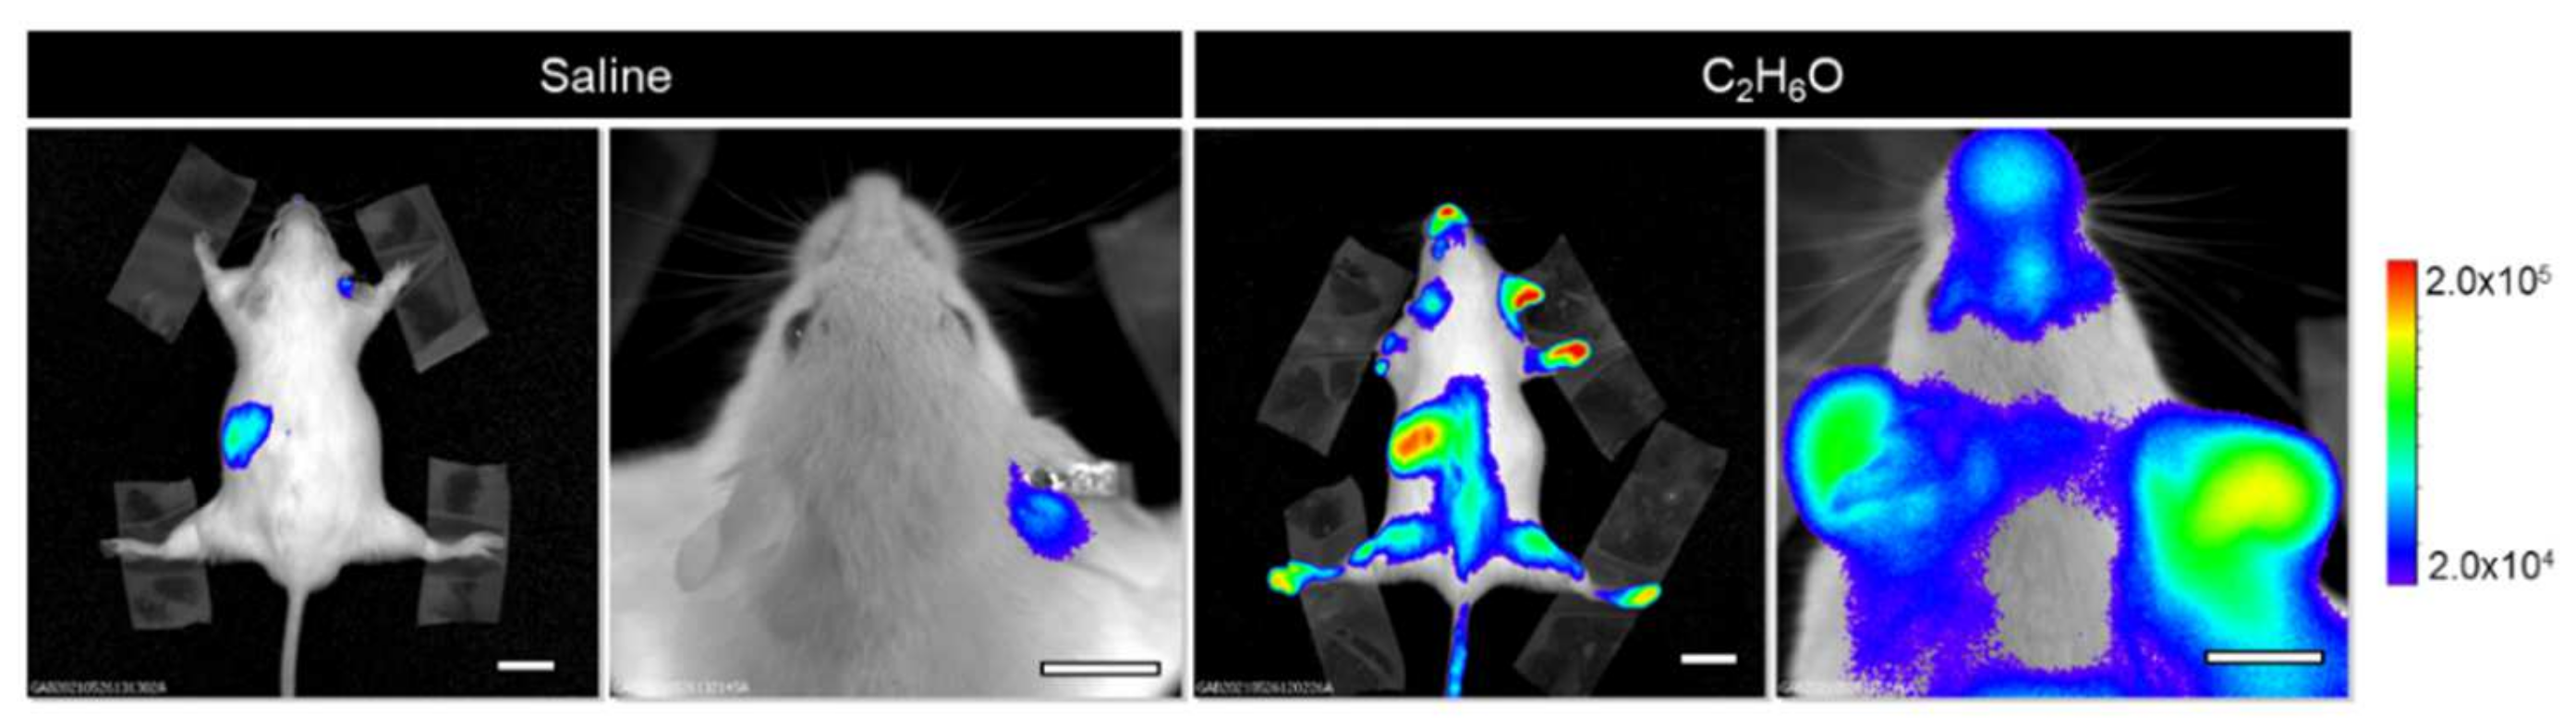

3.1. Alcohol Intake Transiently Modulates Bioluminescence Signals Associated with Cell Proliferation in the MITO-Luc Mouse